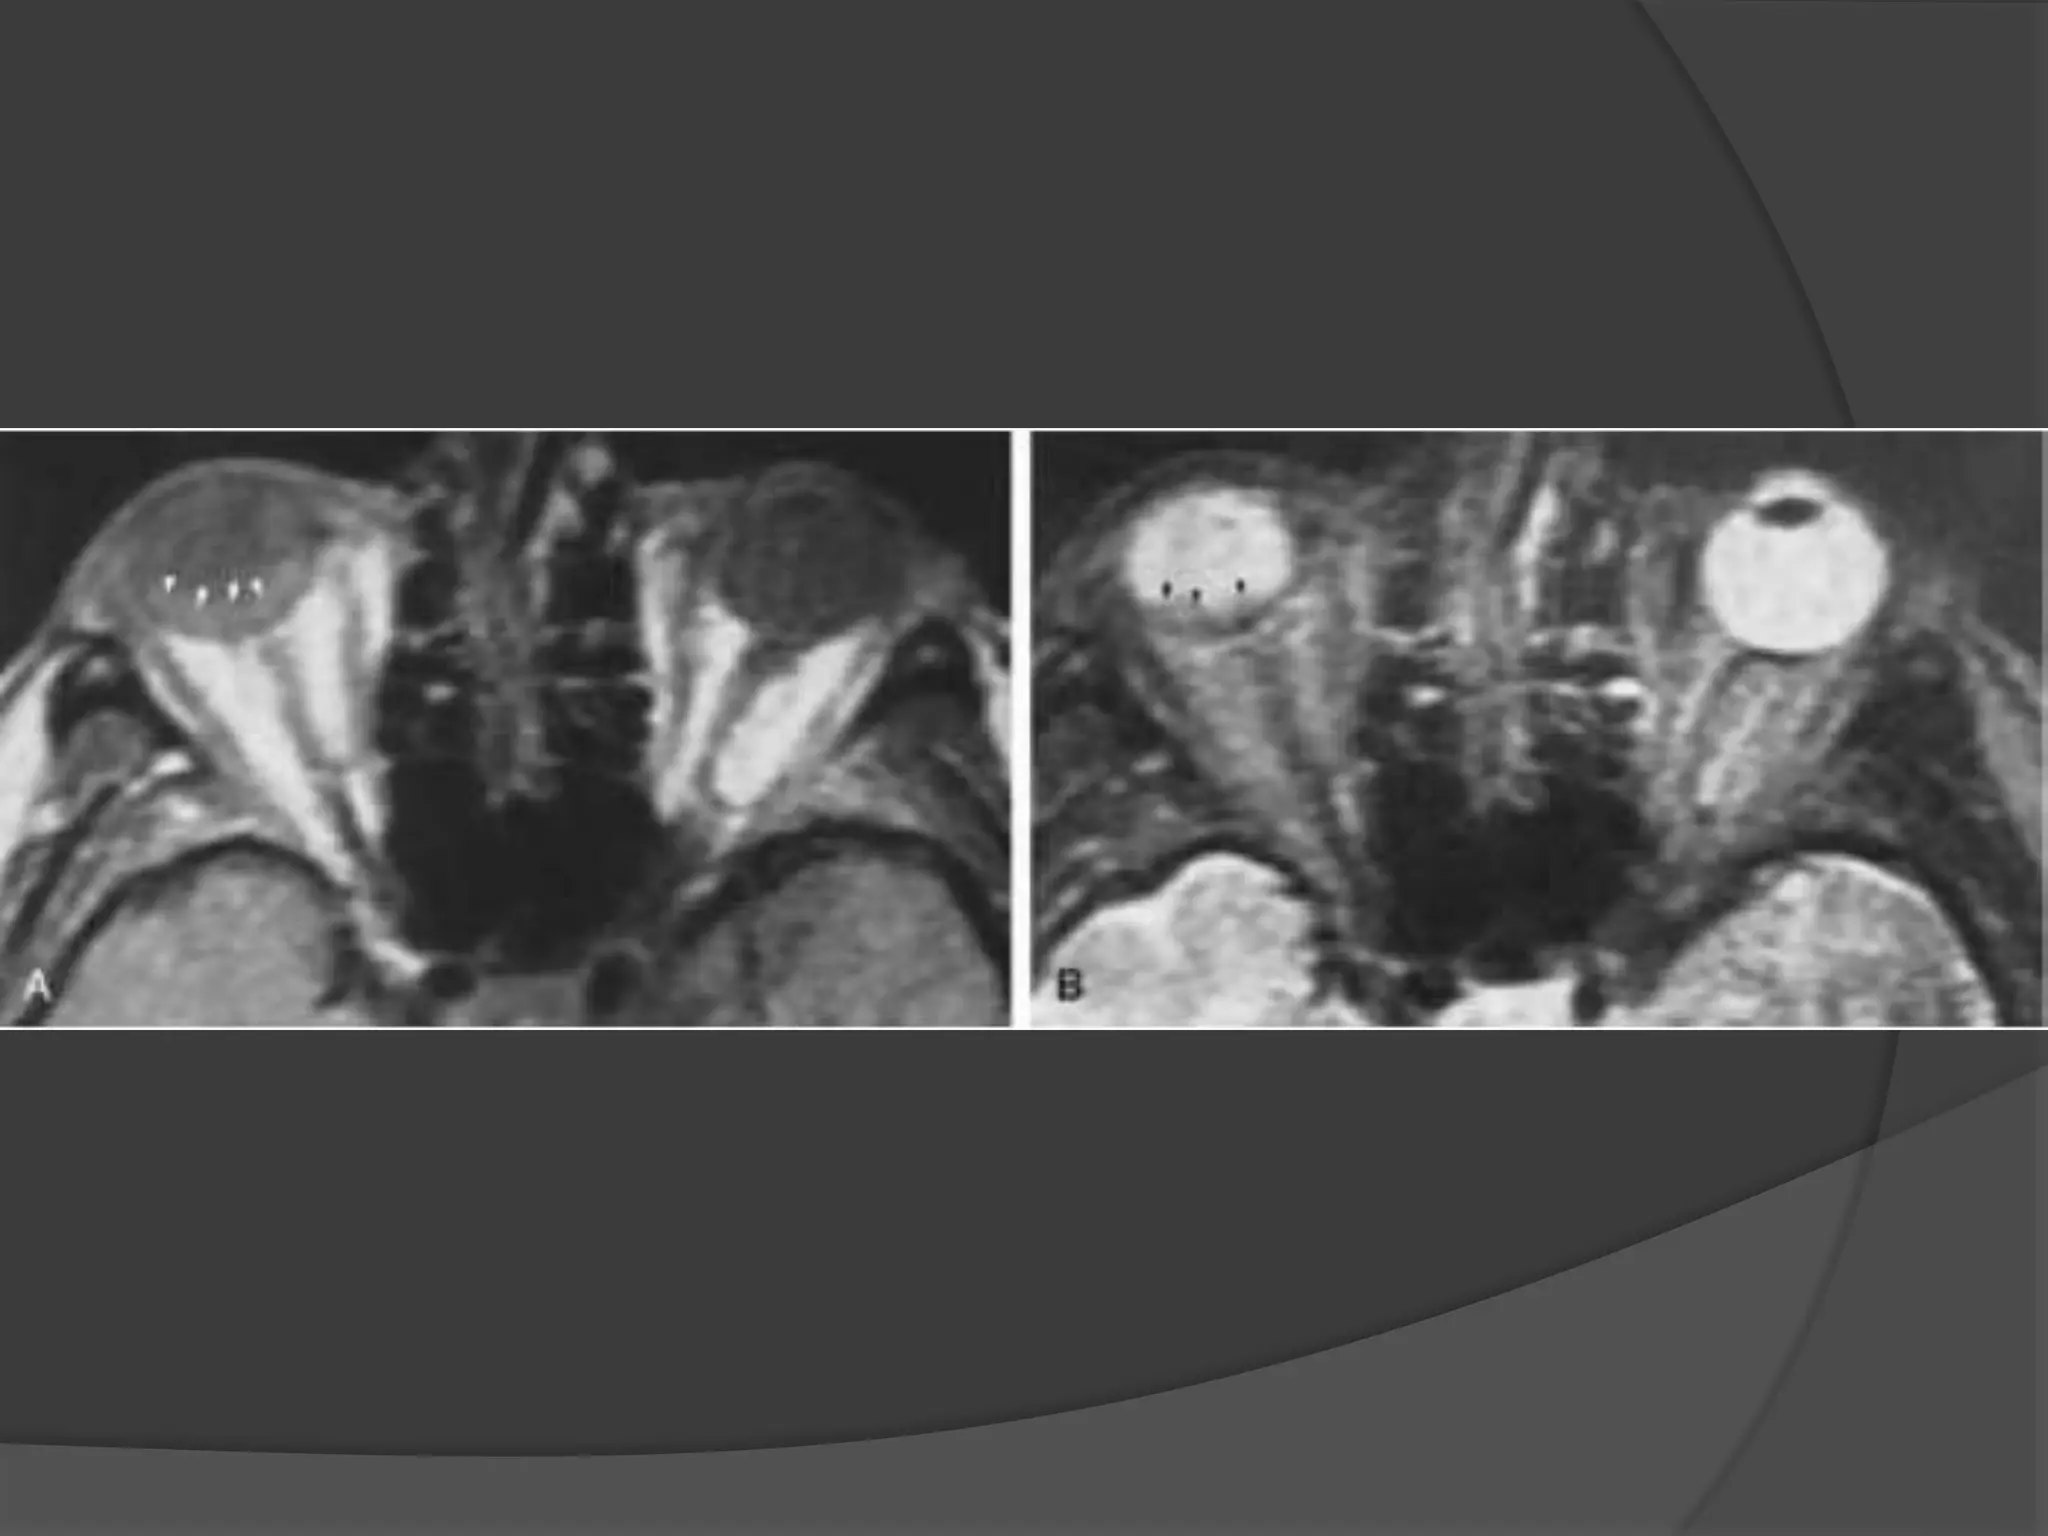

Imaging : MRI is the modality of choice with hyper intense signal of

T2WI due to fluid and edema. Fat Sat contrast enhanced T1WI will show

areas of demyelination. CT relatively insensitive.

Straightening and thickening

of right optic nerve.

Optic Neuritis. CE Fat Sat T1W axial

(B) MR images demonstrate subtle enlargement and enhancement of the left

optic nerve (curved arrow).

T 2 WI (C) demonstrates corresponding increased signal intensity (straight

arrow).